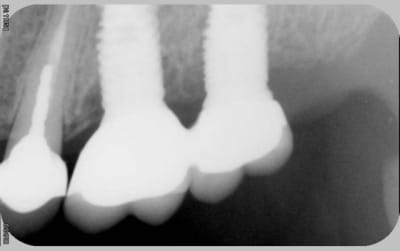

comme promis

voici les cas vus ce mardi (il me manquait encore 10 patients: sur les 5 autres, tout est ok)

ps: la carie et le tartre sur la 7 ont été traités